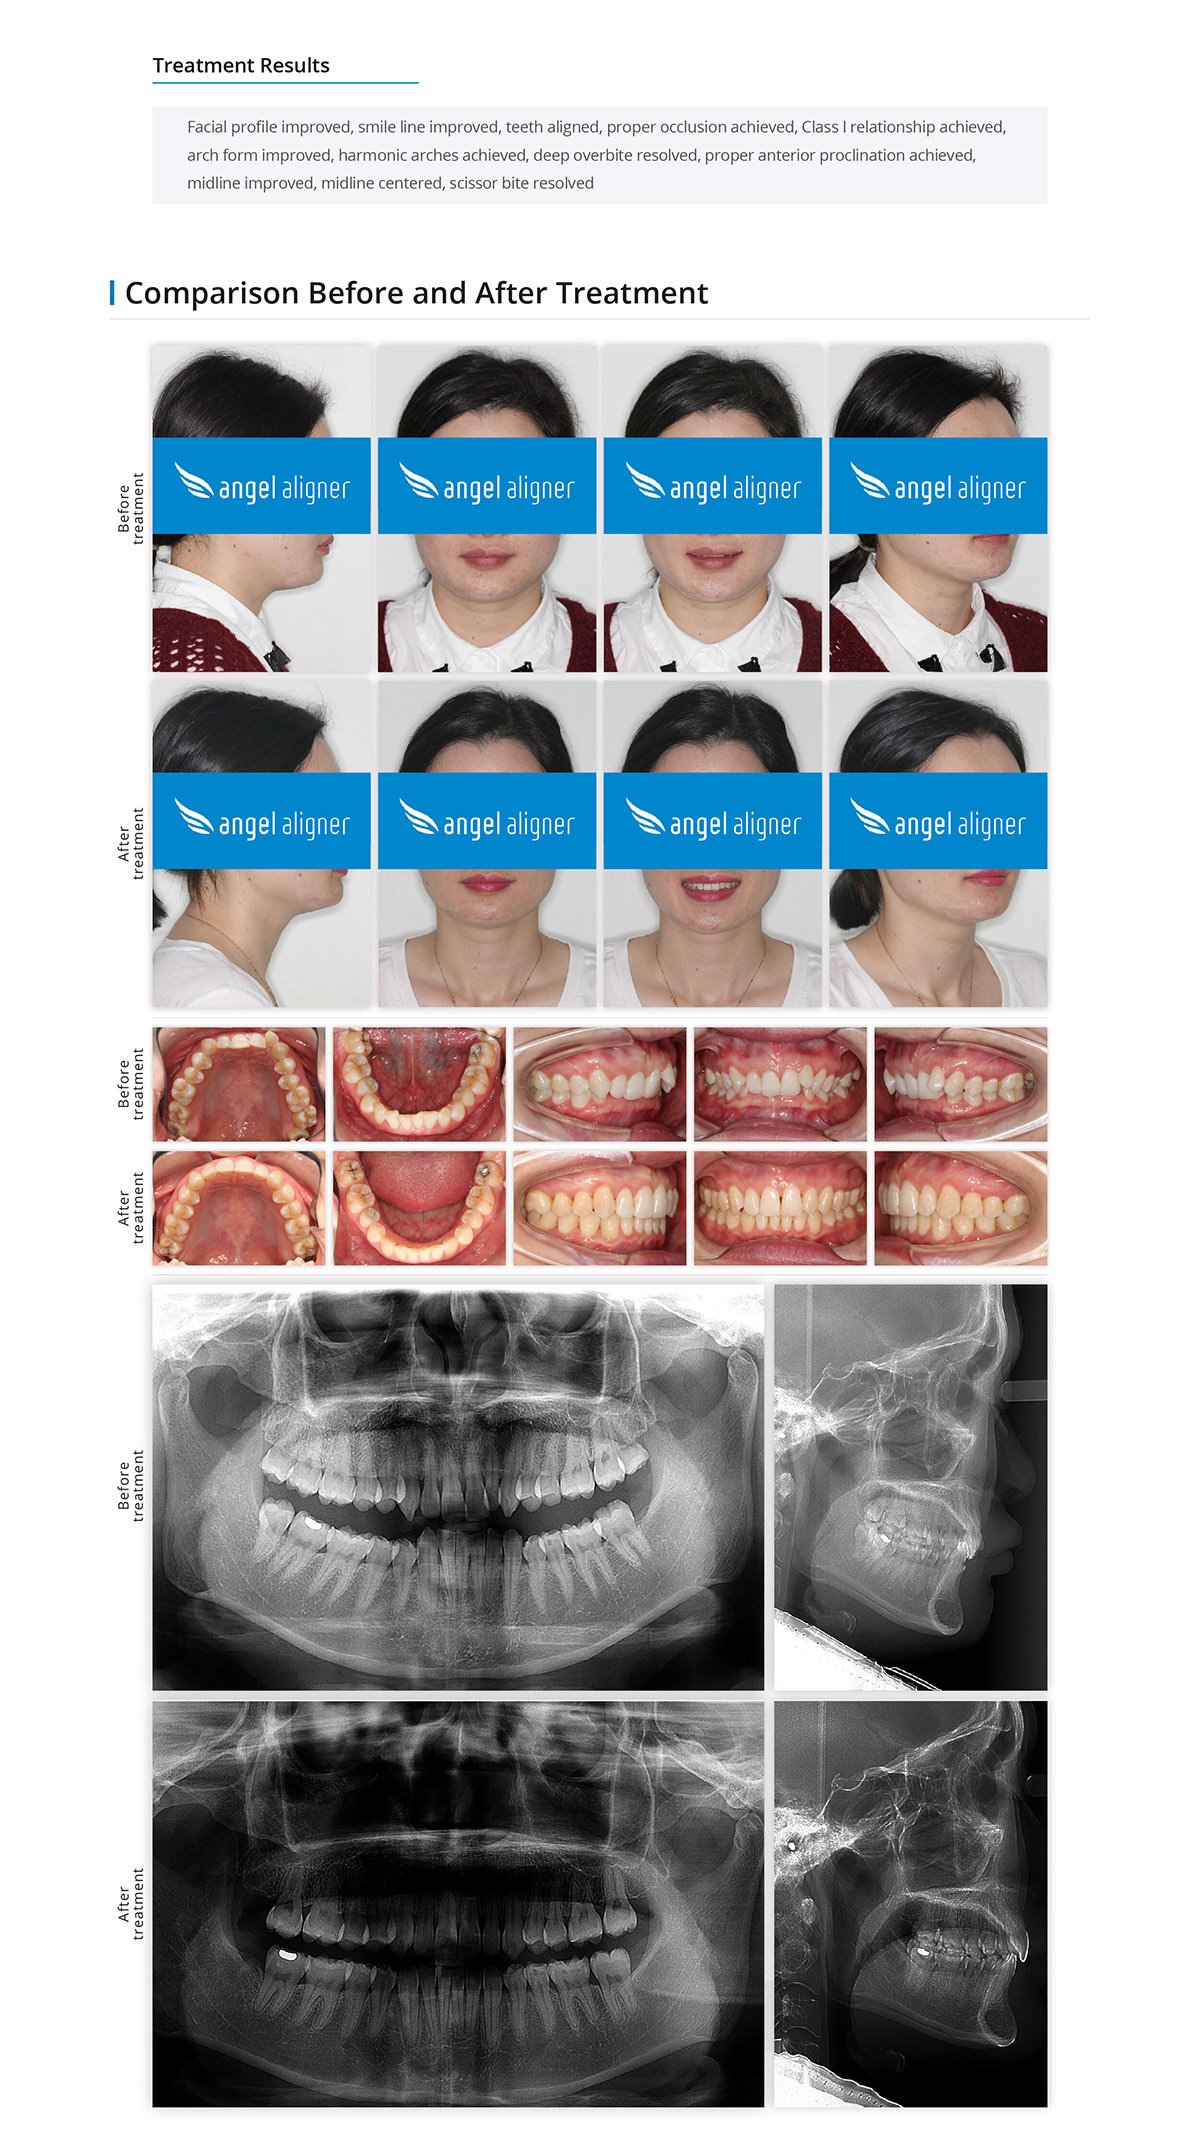

Class II Division 2, Non-extraction Correction, Posterior Scissor Bite

Female, 30 years old

Permanent dentition

Angel Aligner Classic

Total treatment time: 27 months